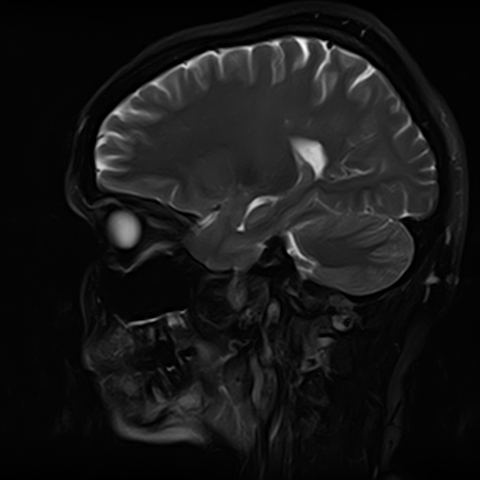

Чаще всего дисфункция височно-нижнечелюстного сустава обусловлена внутренним повреждением, смещением мениска и суставной головки нижней челюсти. Для определения степени смещения внутрисуставных структур выполняется функциональная проба с проведением МРТ в двух положениях:

• с закрытым ртом;

• с открытым ртом.

Магнитно-резонансная томография является наиболее точным и эффективным методом диагностики поражения височно-нижнечелюстных суставов, так как позволяет получить детальную информацию о состоянии не только костей, но и связочного аппарата, хрящей, менисков, жевательных мышц, окружающих мягких тканей.

При проведении магнитно-резонансной томографии на изображениях визуализируются: височная кость, головка мыщелкового отростка нижней челюсти, суставная щель. Помимо костных структур МРТ позволяет оценить состояние мягких тканей – внутрисуставного диска и связочного аппарата височно-нижнечелюстного сустава, жевательных мышц.

МРТ ВНЧС с капой включает в себя два протокола: с открытым ртом и с закрытым ртом. Данная функциональная проба позволяет проследить степень смещения внутрисуставных анатомических структур и оценить биомеханику движений в суставе.

Протокол МРТ ВНЧС предусматривает проведение исследования в двух положениях: с открытым ртом и закрытым ртом. Данная функциональная проба дает возможность оценить биомеханику работы височно-нижнечелюстного сустава.